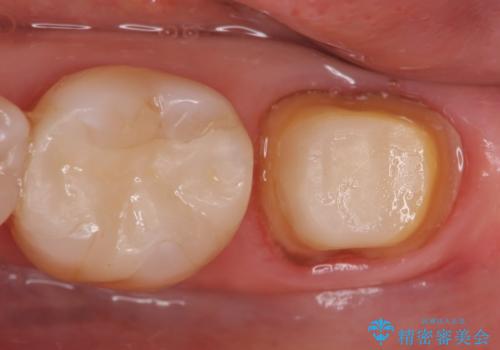

- 他院にて根管治療を行っていたが、痛みが引かないため当院での診療を希望された方の症例です。

改めて再根管治療を行い、症状の緩解を確認後、オールセラミッククラウンによる補綴を行いました。

- オールセラミッククラウン…¥100,000、ファイバーコア…¥20,000費用は治療当時の料金となります